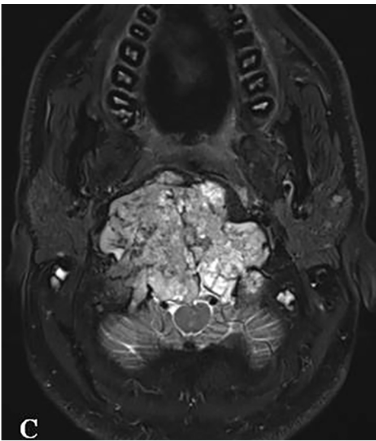

针对颅颈不稳定的问题,手术团队在颈椎的C0、C3、C4及C5椎体上精准置入根钉。这些根钉经过特殊设计,采用曲线方式横向弯曲,使其完美贴合颈椎的生理曲度。此种固定方式在提升稳定性的同时,有效减少了对周围软组织的潜在损伤。根钉植入后,采用Roy-Camille技术完成枕颈融合(C0-C3-C4-C5)。融合过程中,使用生物材料填充椎体间空隙,以促进骨组织生长与愈合,最终增强颈椎的整体稳定性。

需要特别指出的是,固定根钉的曲线形横向弯曲设计,核心目的之一是为患者后续的质子治疗创造出一个无金属干扰的定位与治疗通道。术后CT与MRI复查证实肿瘤已达完全切除,病理学检查确认为典型脊索瘤。术后患者吞咽功能显著改善,颈部疼痛缓解。在恢复数周后,该患者顺利接受了质子治疗。